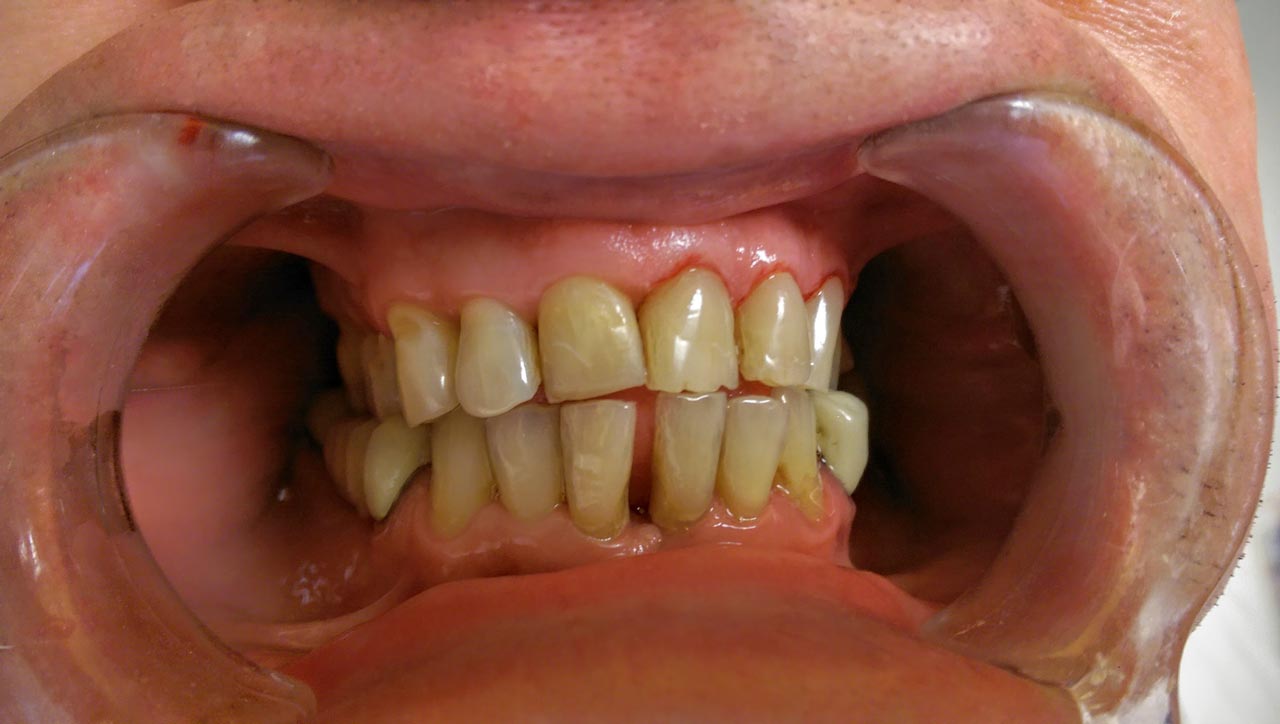

Alsó állcsont teljes rehabilitációja 72 óra alatt

Alsó állcsont teljes rehabilitációja 72 óra alatt, azonnal terhelhető implantátumokkal súlyos paradontitisben szenvedő dohányzó páciens esetében. Az alsó állcsont fogai mind mozogtak az előrehaladott fogágypusztulás miatt.

A fogakat eltávolítottuk, a gyulladt, fertőzött csontot kitakarítottuk, kifertőtlenítettük, majd azonnal implantáltunk.

Svájci, IHDE márkájú, azonnal terhelhető implantátumokat helyzetünk be, és ezekre harmadnapra rögzített, hosszútávú, fémvázas, esztétikus műanyaggal leplezett hidat ragasztottunk be.

Ezt az ideiglenes hidat a sebek gyógyulása miatt használjuk, de tartóssága miatt véglegesként is használható.

A legtöbb esetben, ahogy itt is, 6 hónap múlva porcelán hídra cseréljük, a teljes gyógyulás után.